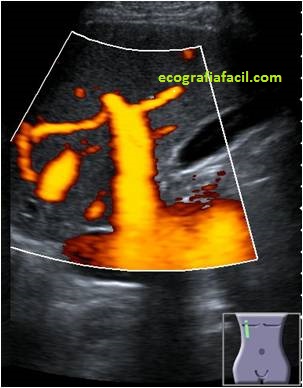

Os voy a dejar una serie de imágenes, quiero que observes como desde la imagen 1 a la imagen 7 el paso del tiempo ha ido cambiando este modo de trabajo, como el avance tecnológico ha ido modelando estos modos de trabajo Doppler en una misma ecoarquitectura muy estudiada como la vena porta en su acceso transcostal, mira:

La imagen 1 era la de un muy buen equipo cuando yo empecé, la imagen 7 es la mejor que he visto hasta hoy día.

La imagen 4 ya fue un cambio brutal en calidad, pero las imágenes 5,6 y 7 son distintas.

La imagen del doppler color, la de la imagen 5, el color es más voluminoso, parece un color espacial y metálico, mucho más sensible y visual.